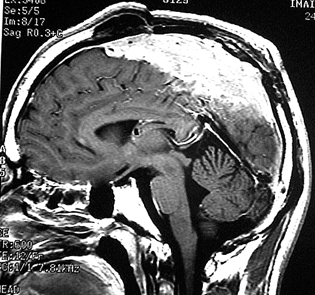

- 下のMRIは66歳の女性に脳ドックで偶然見つかった髄膜腫です.左の写真は1995年,右は2005年です。10年間で全く大きくなっていません

8年間の観察で大きくならなかった髄膜種(左1996年,右2004年)